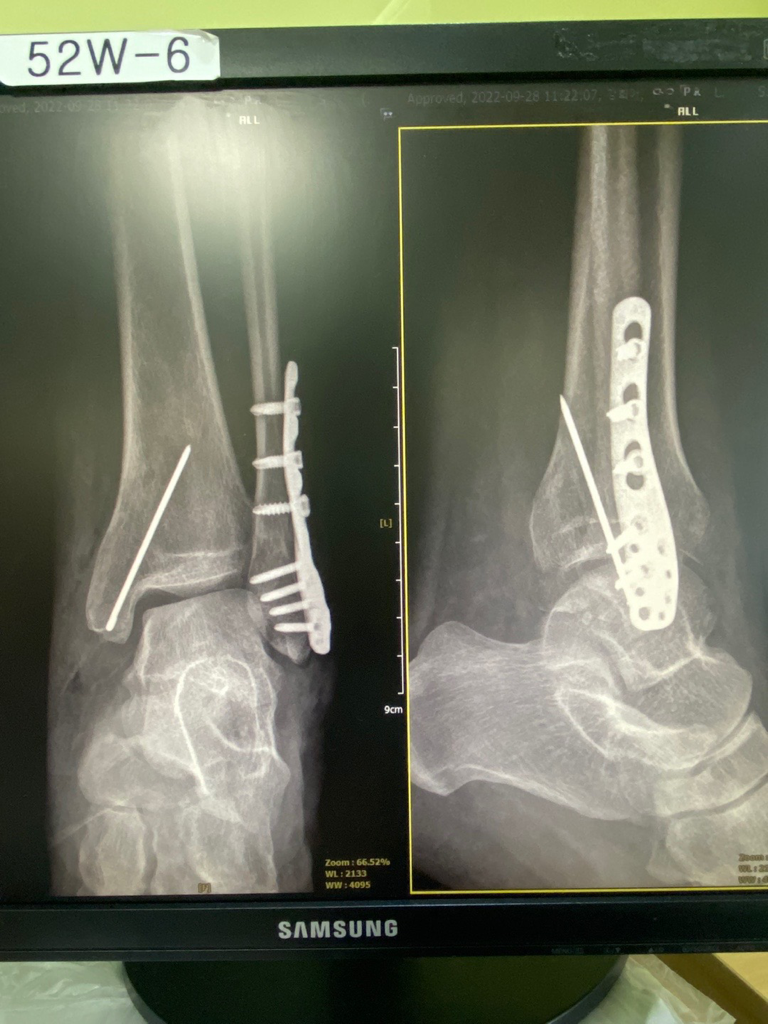

붓고 통증이 심하다면 골절을 염두해두고 정형외과 진료를 반드시 받으셔야 하겠습니다.

추가적인 엑스레이 검사가 필요합니다.